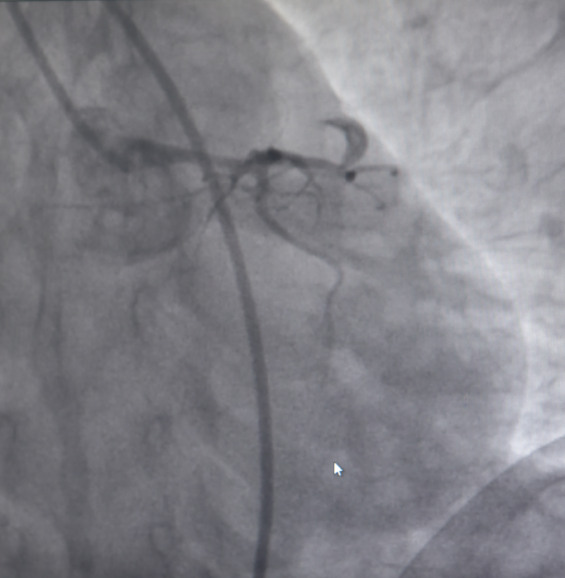

随后,患者立即被送往导管室,揭主任携副主任医师蒋溢为迅速给患者完成了冠脉造影,术中见患者左主干明显变窄,回旋支闭塞,血流TIMI0级,前降支次全闭塞,血流TIMI1级。但此时尚未能明确患者是否为冠脉痉挛或冠脉自发夹层,揭英纯和蒋溢为副主任医师当机立断,为患者快速完成了血管内超声检查,原来是冠状动脉自发夹层!考虑到患者冠脉已经闭塞,遂在IVUS指导下选择切割球囊精准对闭塞血管进行切割扩张,恢复回旋支及前降支正常血流。

左主干至回旋支、前降支自发性冠状动脉夹层、血肿压迫真腔

血管再通,血流恢复正常